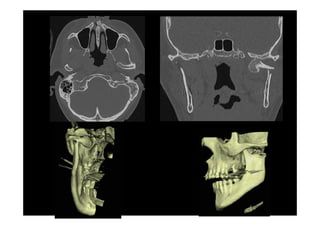

Fracturas complejas de la cara

Fracturas del Complejo Naso-

Etmoido-Maxilo-Fronto-Orbitario

Fracturas complejes de la cara

Fracturas Cigomáticas Complejas